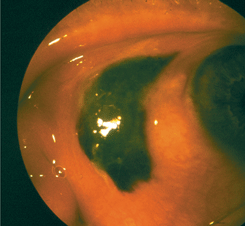

Деструктивная базалиома ;(см. рис. 4 на цветной вклейке) характеризуется более быстрыми темпами агрессивно инфильтрирующего роста опухоли. Веко разрушается на всю его толщу, что приводит к образованию больших дефектов. Опухоль рано прорастает в полость орбиты.

Рисунок 4. Деструктивная форма базально-клеточного рака